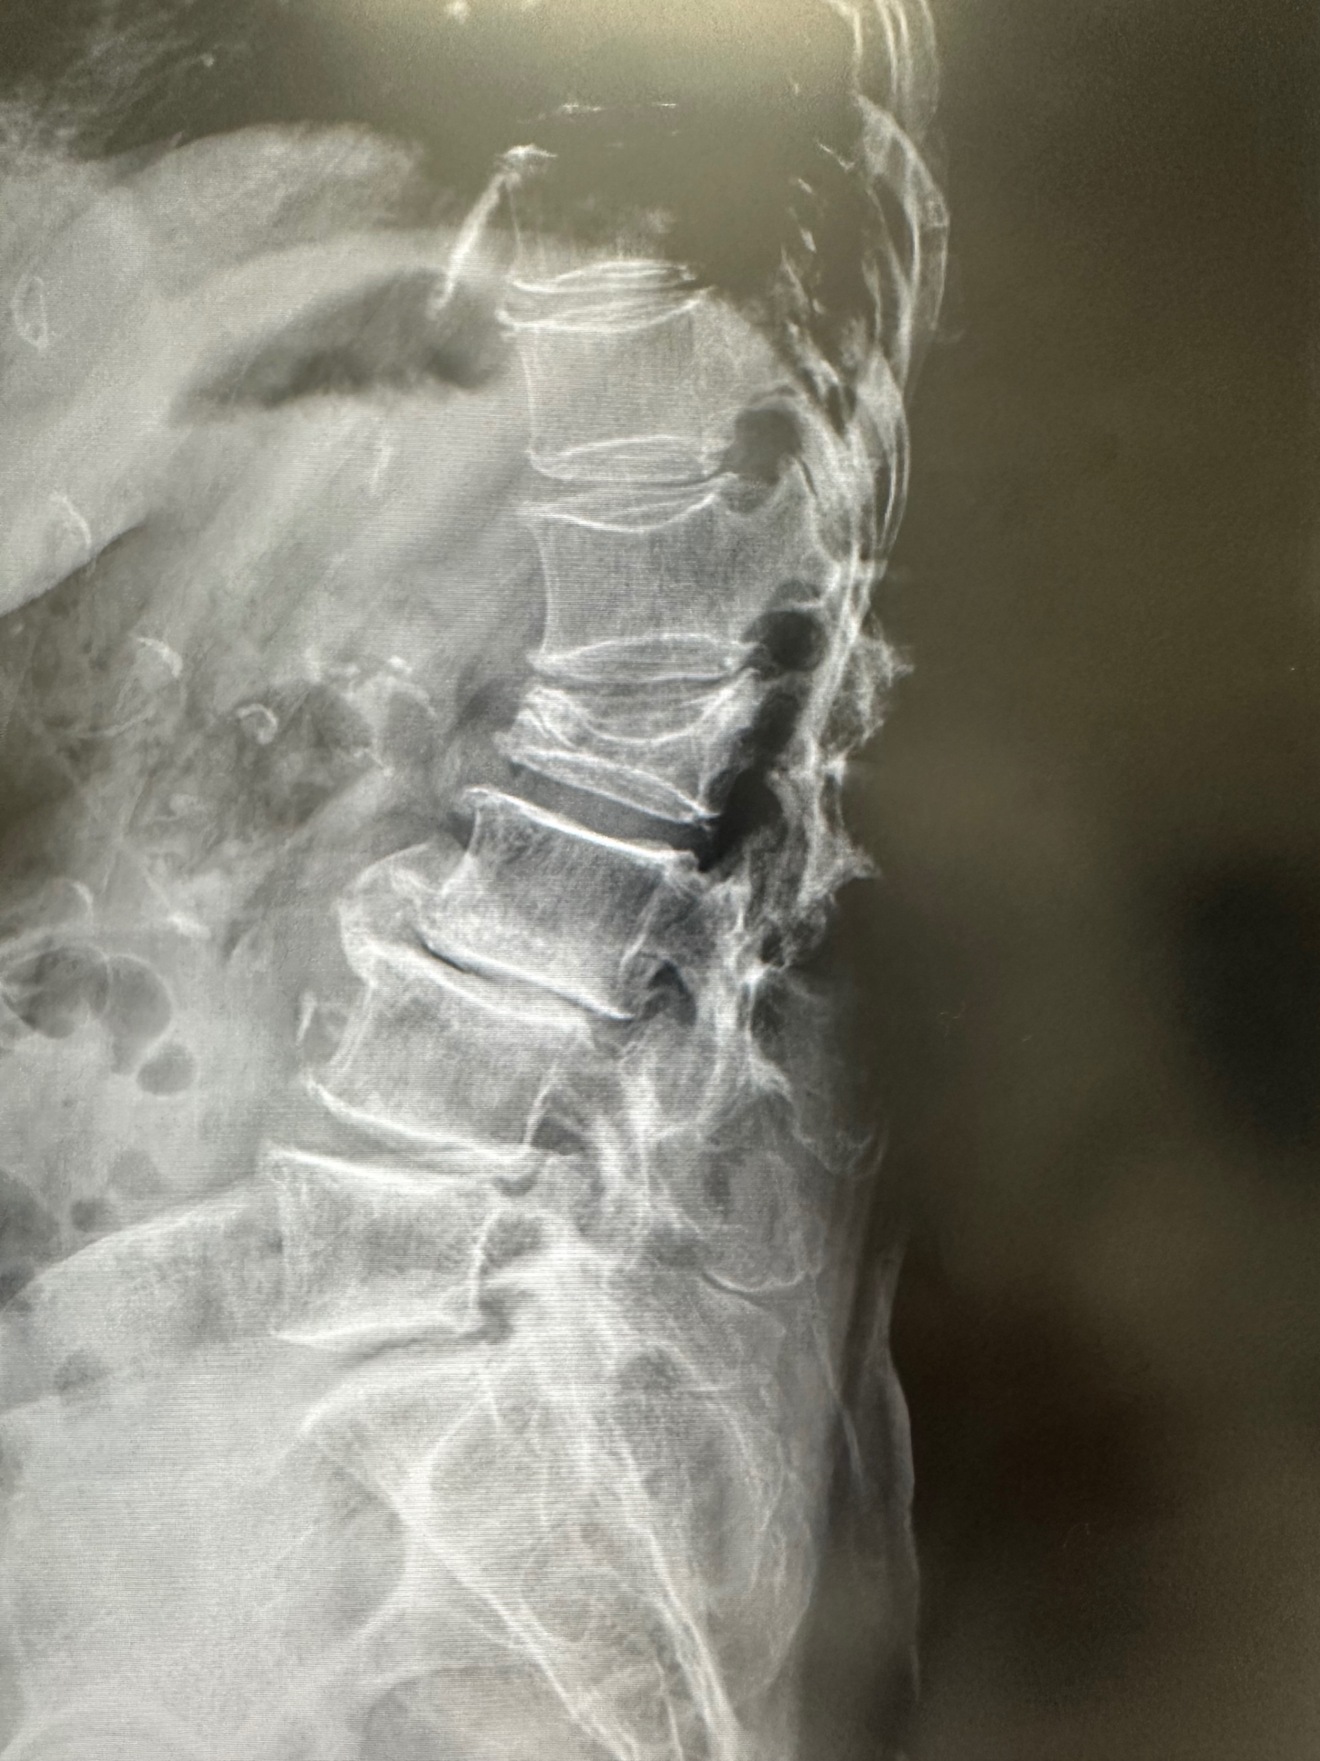

è °æ€å§è¿«éªšæ(è °ã®è骚ã®éªšæ)

å°»ãã¡ãã€ãããšã§ãå°»ãã軞å§ãããããè

°ã®éªšãã€ã¶ããããã«éªšæããŸããåœç¶è

°ãçããªãåããªããªããŸãã

æ²»çã¯åããšçãã®ã§ã³ã«ã»ããã§å®éã«ããããã»ã¡ã³ãã§åºå®ããæè¡ãªã©ããããŸãã

ãŸãçã¿ãç¡ãç¥ããªããã¡ã«æããŠããããã€ã®éã«ã骚æããšåŒã°ããŠãããã®ããããŸããæè¿èº«é·ãçž®ãã ãªãšæã£ãããããé ãããŠãããããããŸããã